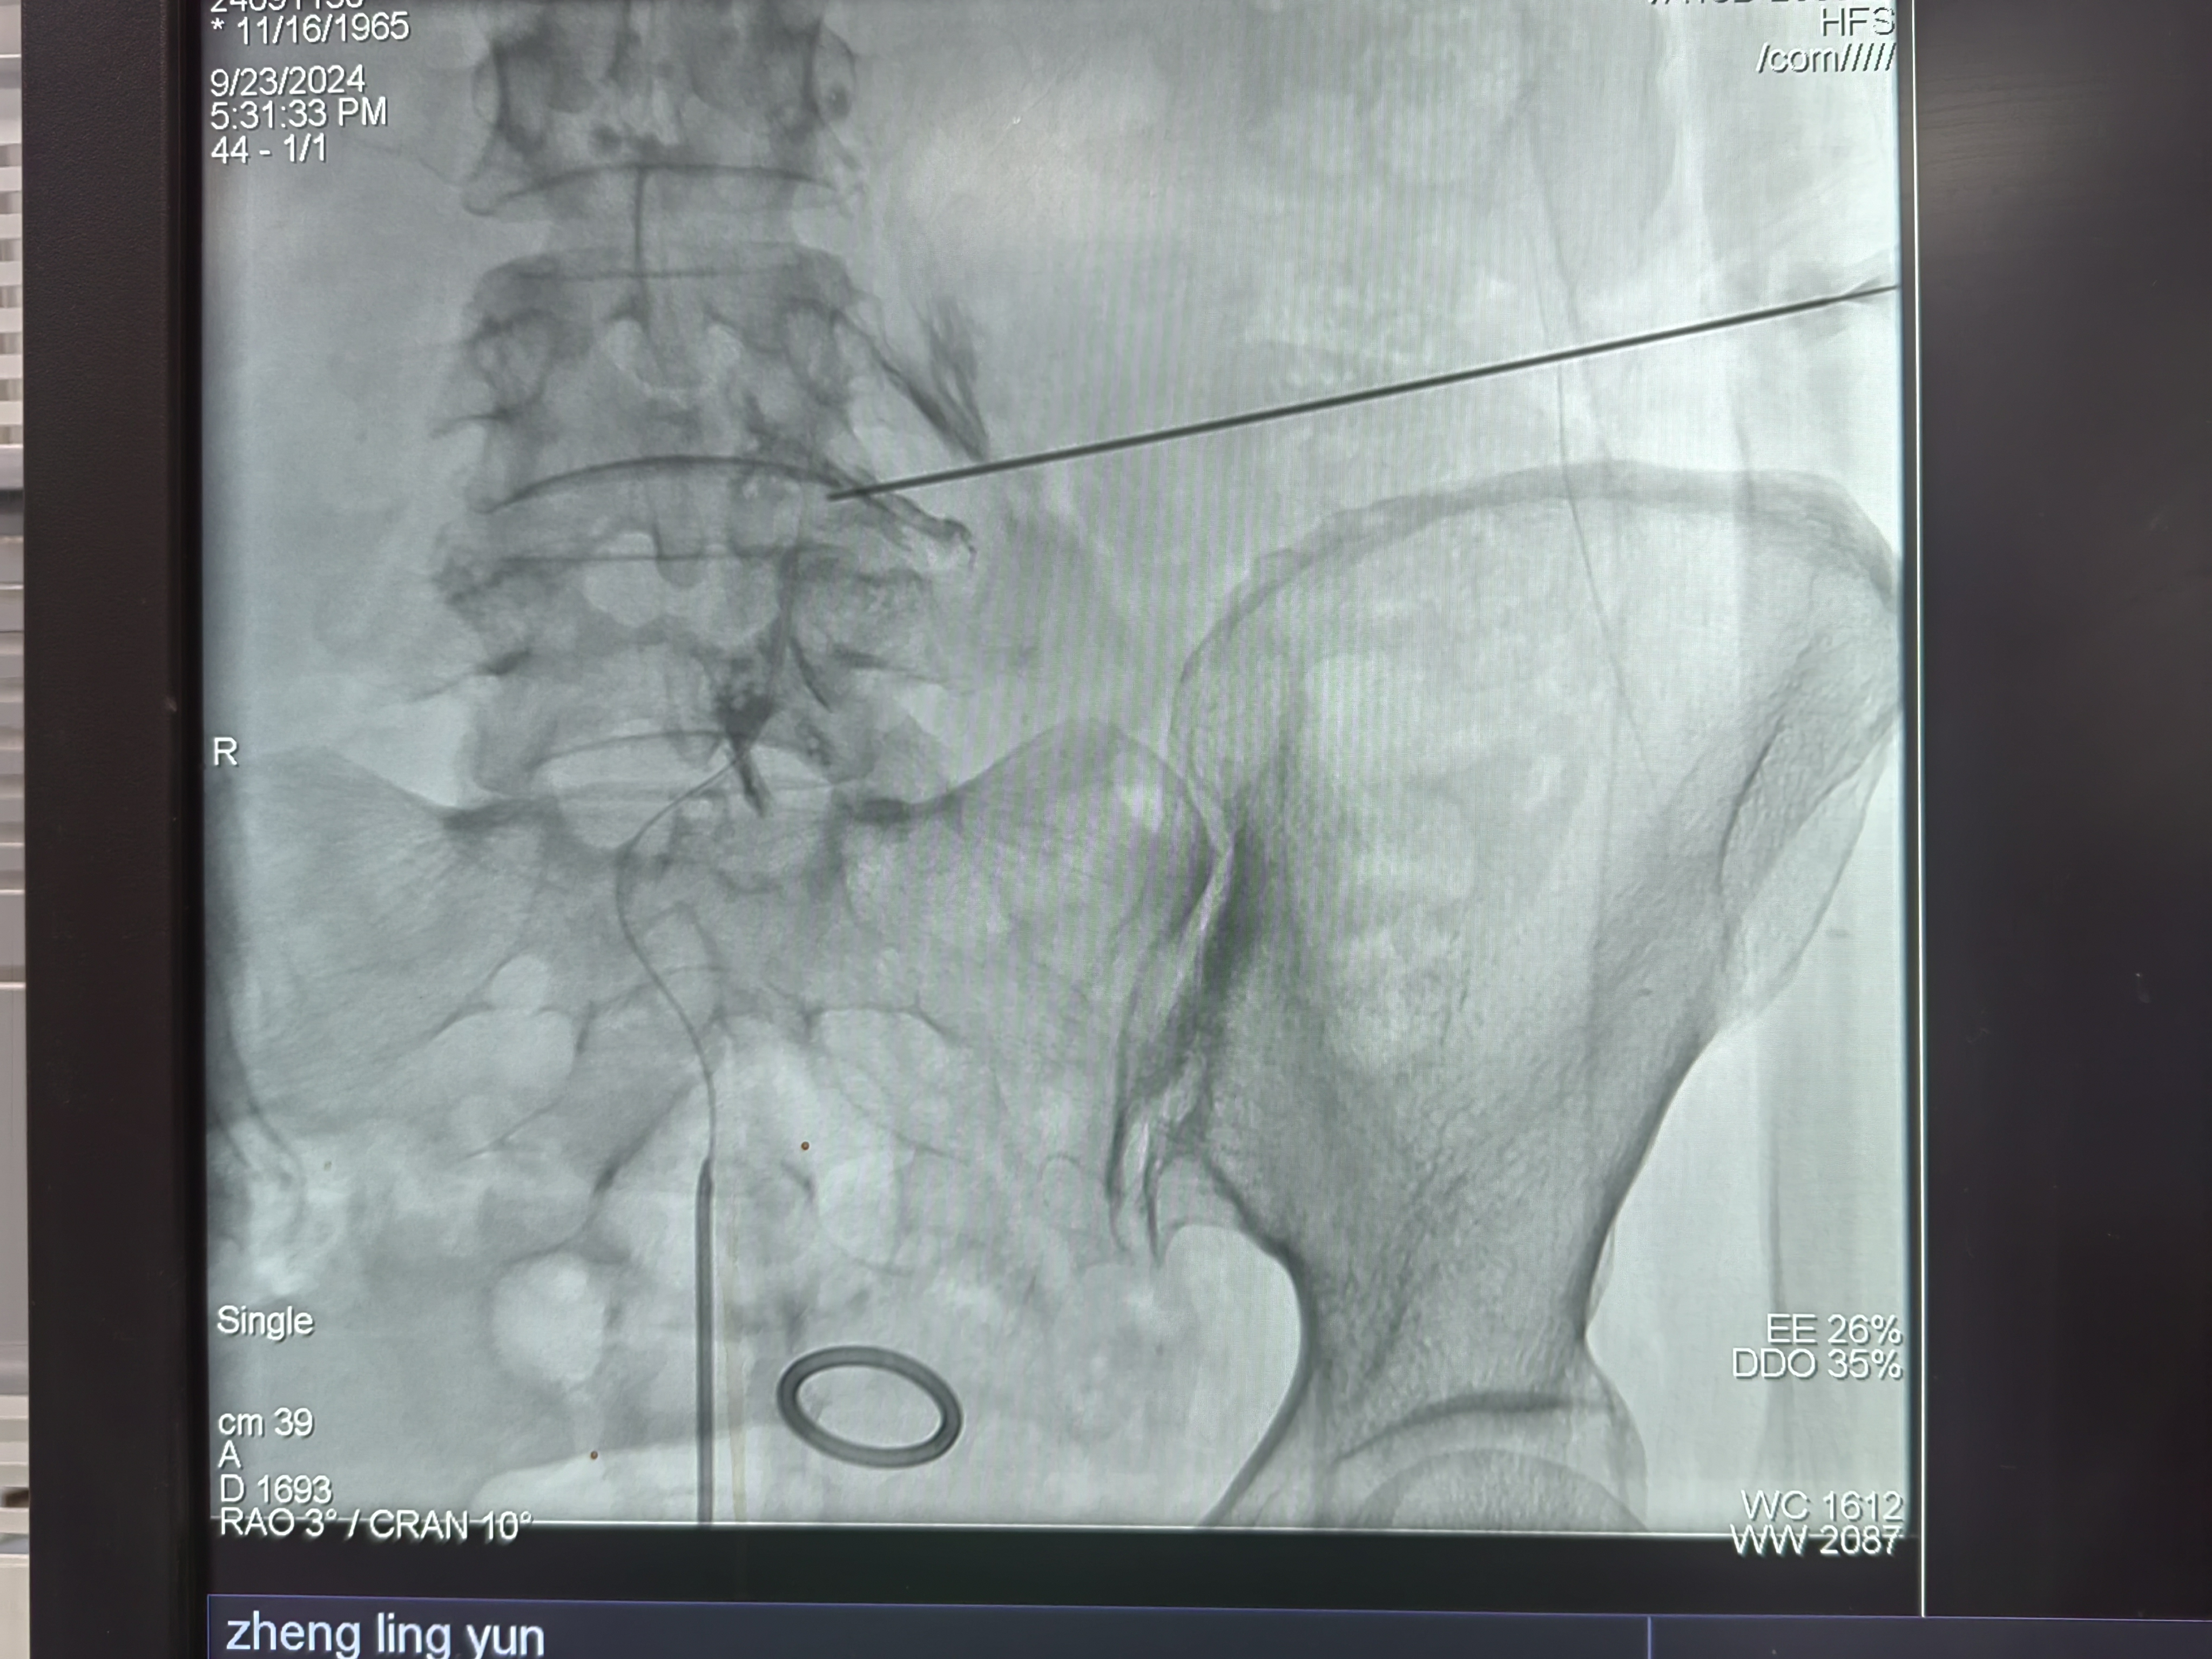

腰椎C臂透视下